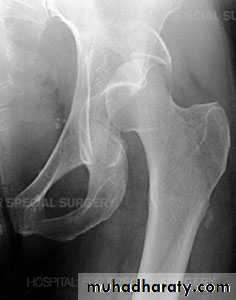

INTRA CAPSULAR FRACTUREfracture neck femur

The femoral neck is the commonest site of fractures in the elderly.

Pathological anatomy and classification

The most useful is that of garden which is based on amount of displacement apparent in the pre-reduction x-ray of the neck femur.

Radiological examination

two questions must be answered.

Is there a fracture?

Is it displaced ?

:Radiological classification

GRADE 1

:the femoral head is in its normal position or tilted into valgus and impacted on the femoral stump.

GRADE 2

The femoral head is normally placed and the fracture line may be difficult to diagnosed

GRADE 3

The femoral head tilted out of position and the trabecular marking are not in line with those of innominate bone.

GRADE 4

The femoral head trabeculae are normally aligned with those of innominate bone.